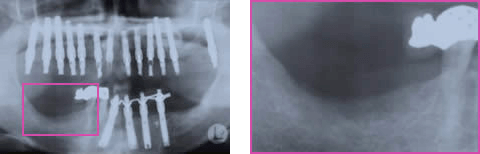

インプラント治療を希望し来院され、全顎的に高度の骨吸収を認めました(図1)。術前のCTデータをSimplantsにより3D構築し診断・計測したところ、下顎左側臼歯部の歯槽骨頂-下歯槽菅距離は第一第二大臼歯部で約9mmと近接、(図2)また、同部のハンスフィールド値からは歯槽頂部における皮質化の昂進を認めました(図3)。インプラント埋入には垂直的な骨高径獲得が必要不可欠であることから、vertical ridge augmentationを予定すると共に再生すべき垂直的骨量が約8mmであること、および同部の骨質から難易度の高さが予想されます(図4)。

術後13週時のパノラマX線写真では予定した骨高径が得られており、移植骨と母床骨との境界は不明瞭でした(図8)。術後24週時のX線所見では予定した骨高径が得られており(図9)、翌週に同部にインプラントを4本埋入、造成した骨には豊富な血流が認められ、骨質は比較的硬く初期固定は十分に得られました(図10)。インプラント埋入後3ヶ月時にはオステオインテグレーションの獲得を確認し、現在プロビジョナルレストレーションにて機能負荷を開始しているが経過は良好です(図11)。

図1:初診時パノラマX線写真

図6:1回目GBR後36week 移植骨の吸収

下顎左側インプラント埋入前